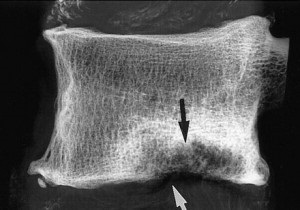

Foto: multiple SHmorlja hernie

Foto: hernia SHmorlja centrală